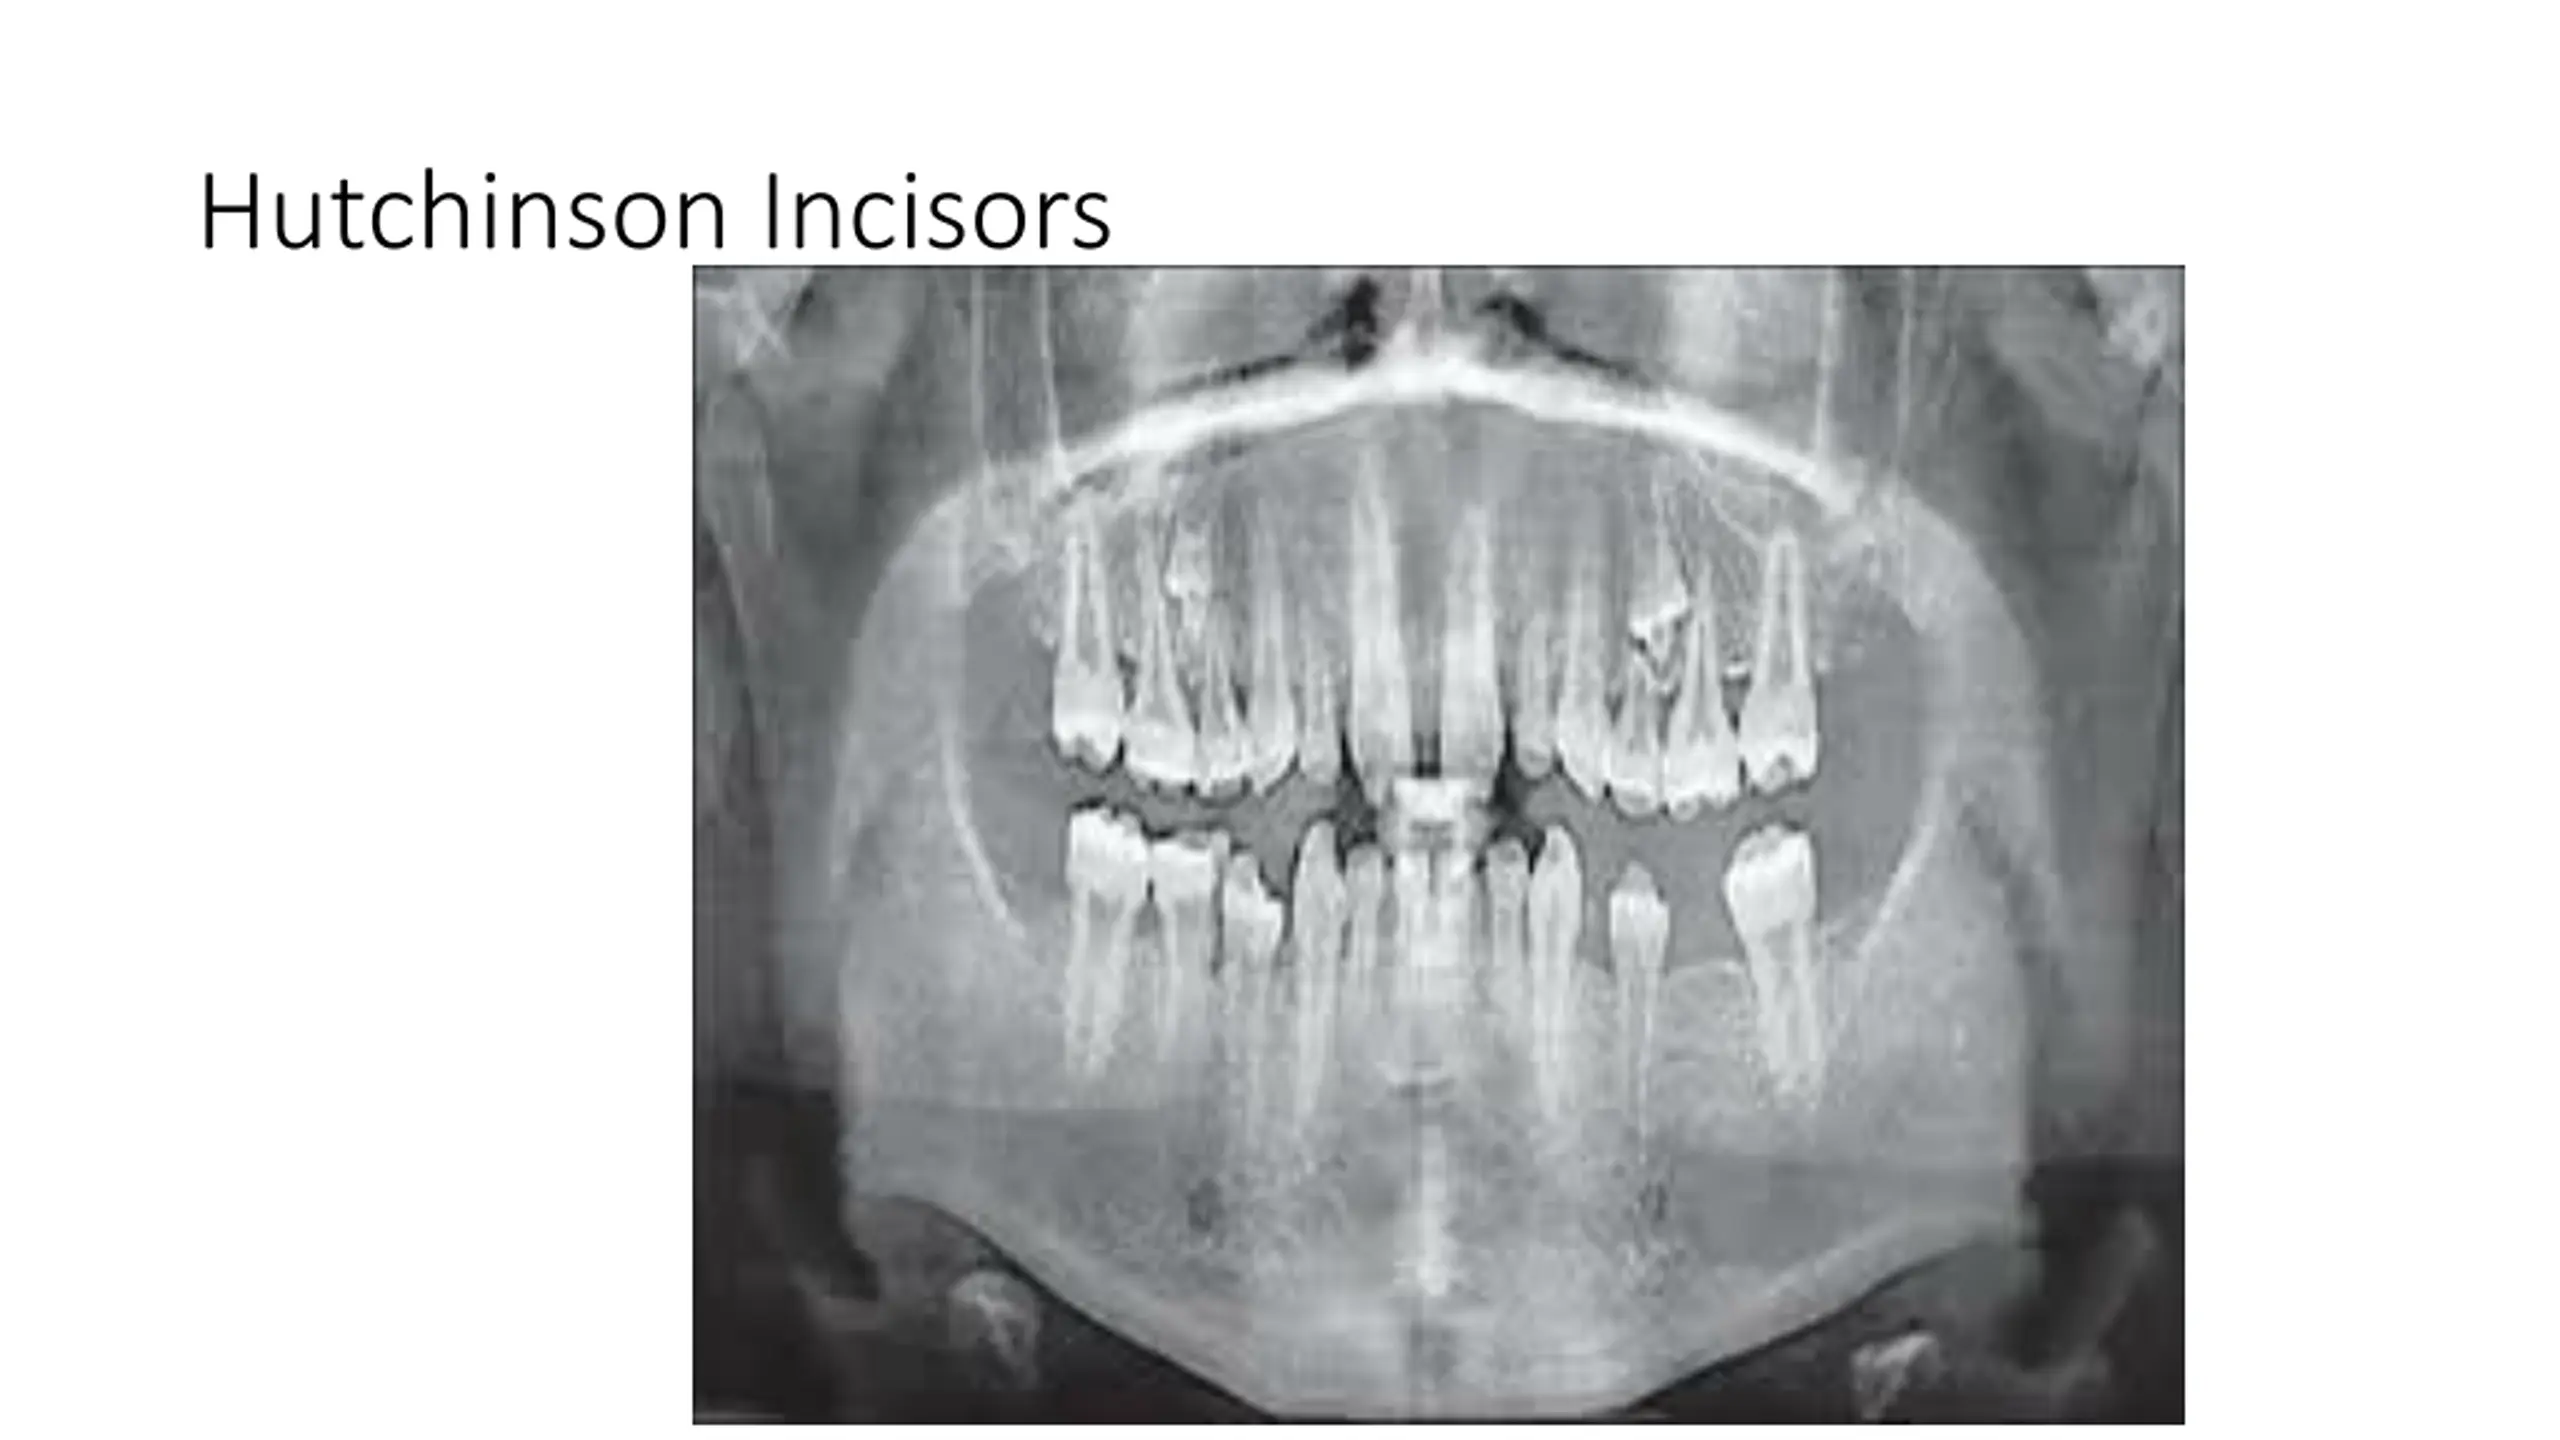

True Anodontia, Partial True Anodontia, Partial False Anodontia, Mesiodens/Supernumerary, Microdontia, Marcrodontia, Gemination/Right Fusion/Left, Peg-Lateral, Fusion Two Roots/Two Crowns, Dens in dente, Dilaceration, Concresences, Taurodontia, Hypercementosis, Amelogenesis Imperfecta, Dentinogenesis Imperfecta, Hutchinson Incisors, Mulberry Molars, Mental Foramens - Radiolucent.